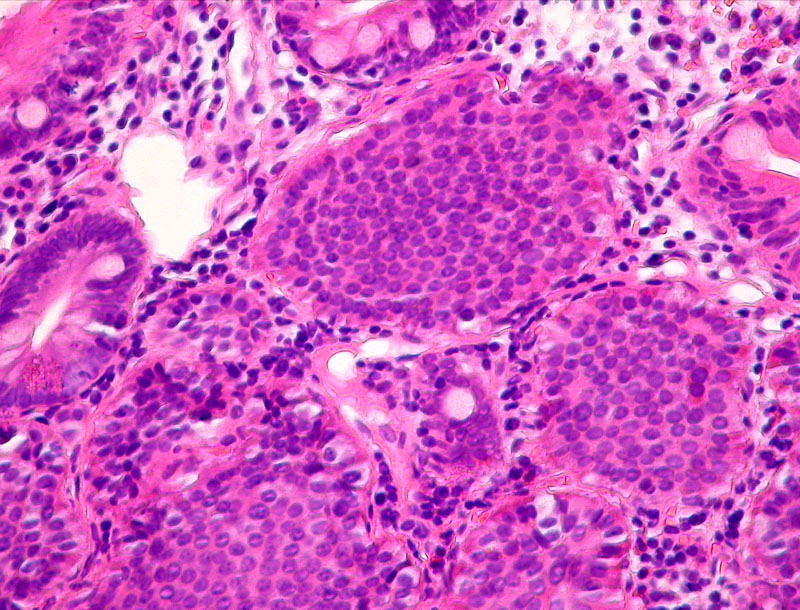

Carcinoid of ileum

Relatively sharply circumscribed submucous tumour.

Alveolar arrangement of the tumorous cells.